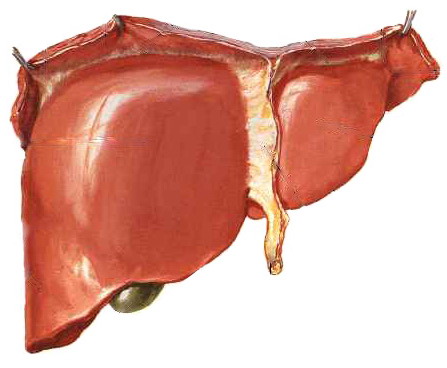

цирроз